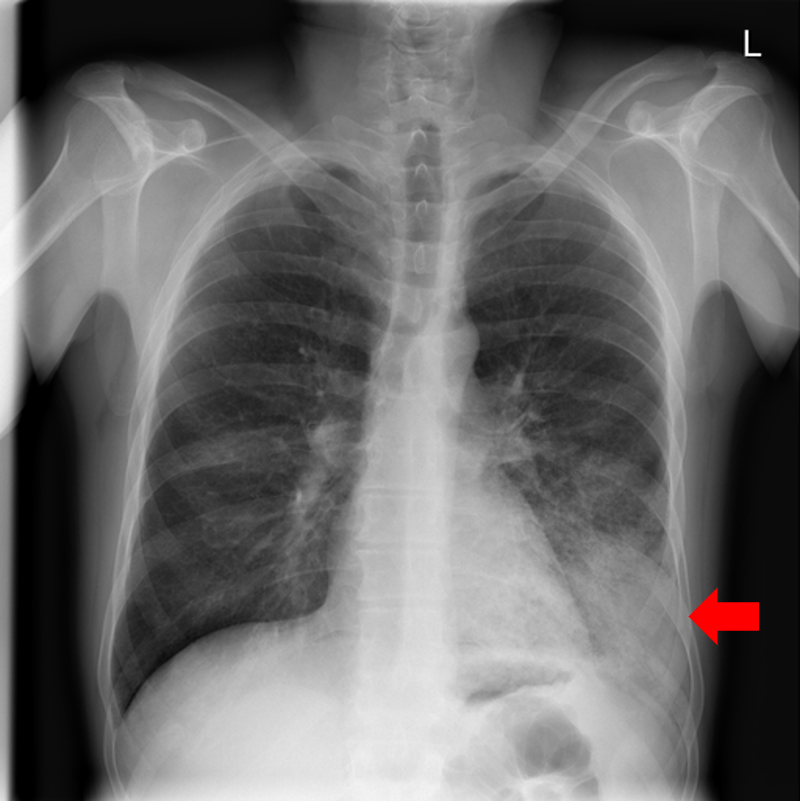

Refer to caption

(a) Pleural effusion

(b) Emphysema

(c) Mediastinal mass

(d) Scoliosis

(e) Multiple bony lesions

(f) Pneumothorax

(g) Heart enlargement

(h) Pneumoperitoneum

Figure 10: Typical CXRs with a lesion from among the top 1,000 CXRs most likely to have an abnormality according to the logarithm posterior probability out of the 13,863 abnormal CXRs excluding those with a pneumonia-like lung opacity. The lesion is indicated with a red arrow if applicable.

Figure 10 shows CXRs suggested to have an abnormality different from pneumonia-like lung opacity with the logarithm posterior probability. These CXRs are the top 1,000 CXRs most likely to have an abnormality out of the 13,863 abnormal CXRs.